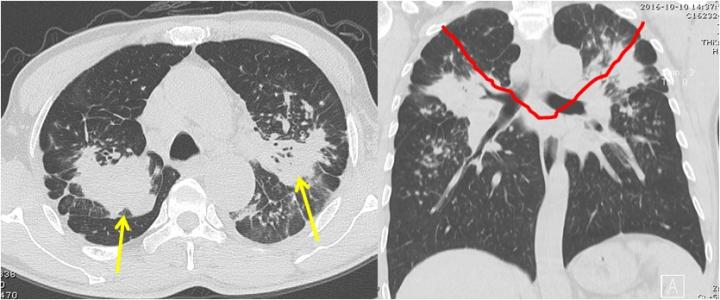

2. 胸部X线表现:以密度较低的类圆形小阴影为主,直径多小于1.5mm,广泛分布各肺区,也可有不规则小阴影。偶有3mm大小密度较低的阴影。可有程度不同肺气肿及胸膜改变。很少有大阴影。国内仅见到I、II期,III期极少见。炭黑尘肺I期表现:有一不定期量密度较低的,肯定的类圆形小阴影,肺纹理尚可辨认。II期:有多量的密度较低的类圆形小阴影,分布范围超过4个肺区,肺纹理通常部分消失。或有很多量的小阴影,分布范围达到4个肺区,肺纹理通常消失。